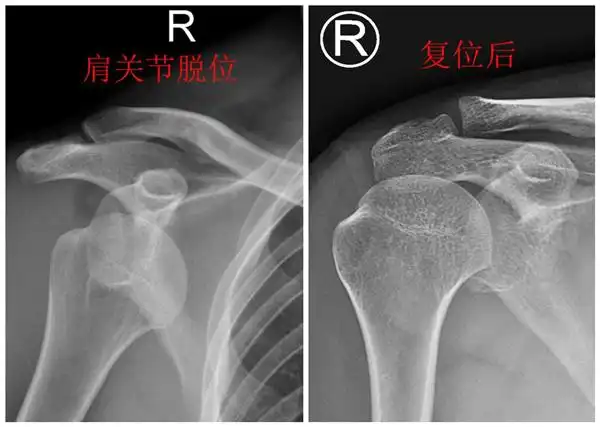

视频教学:简单实用"外展外旋法"复位肩关节前脱位

肩锁关节脱位手术治疗及康复第一周